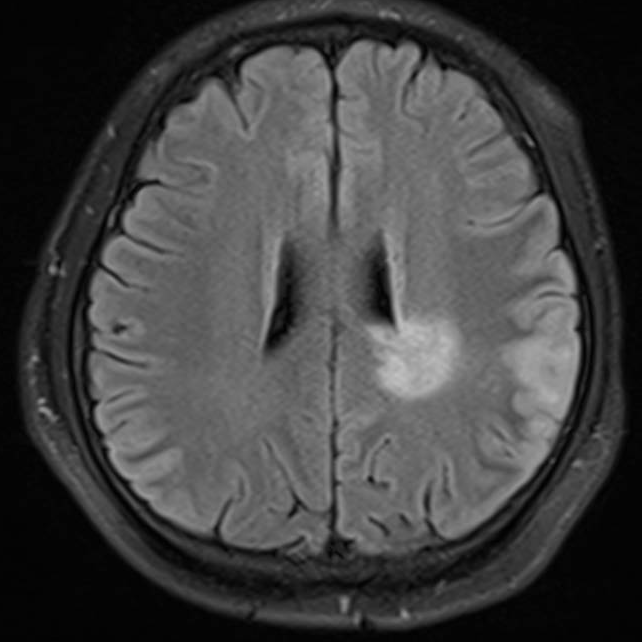

医生要求紧急做颅脑MRI,影像很快就传到了电脑上(图1-6)。医生解释,小脑蚓部占位考虑“脂肪瘤”,另有侧脑室旁白质脱髓鞘和左侧额顶叶皮质性脑炎的改变,“癫痫”可能为“继发性癫痫”。

图6 侧脑室旁病变T2压水压脂